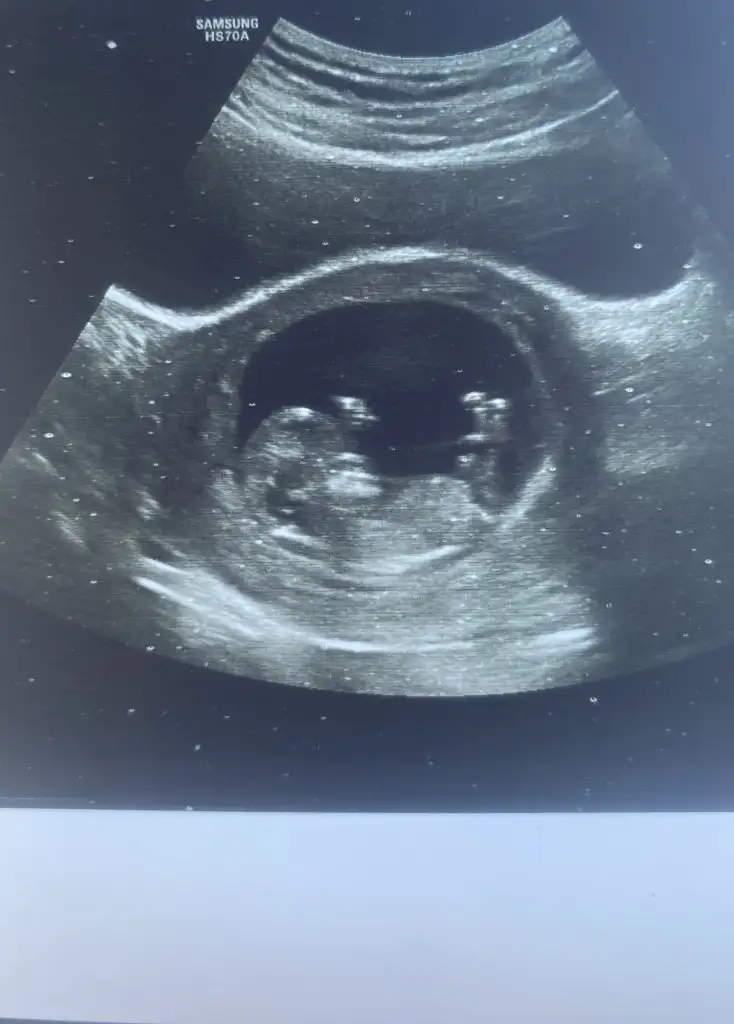

Merhaba benimkini de tahmin edebilir misiniz acaba :)Heyecanını anlıyorum ama çok küçük daha bebiş, kese şekli de çok net çıkmamışRabbim sağlıcakla kucağınıza almayı nasip etsin

Oy maşallah subhanallahMerhaba benimkini de tahmin edebilir misiniz acaba :)Eki Görüntüle 3471936

Bu da benimki teyzesi, sen bir tahminde bulunur musunMerhaba benimkini de tahmin edebilir misiniz acaba :)

Bence erkek olacak neden bilmiyorum bende hamileyim öyle hissettim bide bana tahminde bulunur musunuz 13 haftalık olduBu da benimki teyzesi, sen bir tahminde bulunur musun

Pamuğum sanki erkek gibi geldi bana, teyzoşu onu yesin. Sağlıcakla gelsin inşallah bebişlerimiiiizBence erkek olacak neden bilmiyorum bende hamileyim öyle hissettim bide bana tahminde bulunur musunuz 13 haftalık oldu